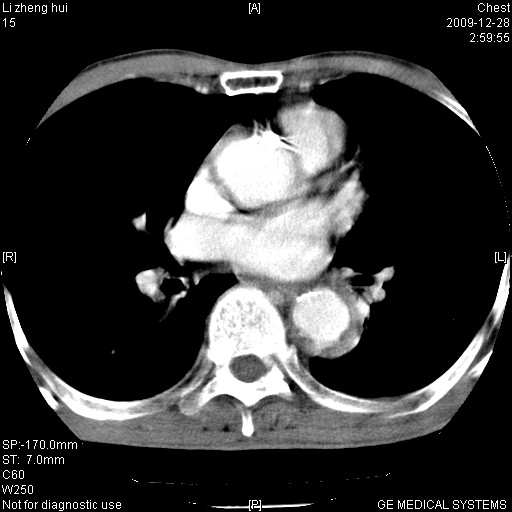

标题: CT23859:胸主动脉瘤

男  79岁 胸部痛急诊入院,晚上做的增强

考虑主动脉瘤?(增粗、钙化、壁血栓?)

动脉瘤伴附壁血栓

1)考虑胸主动脉壁间血肿或夹层动脉瘤。2)多发性肝囊肿。

1)考虑胸主动脉附壁血栓或夹层动脉瘤。2)多发性肝囊肿。